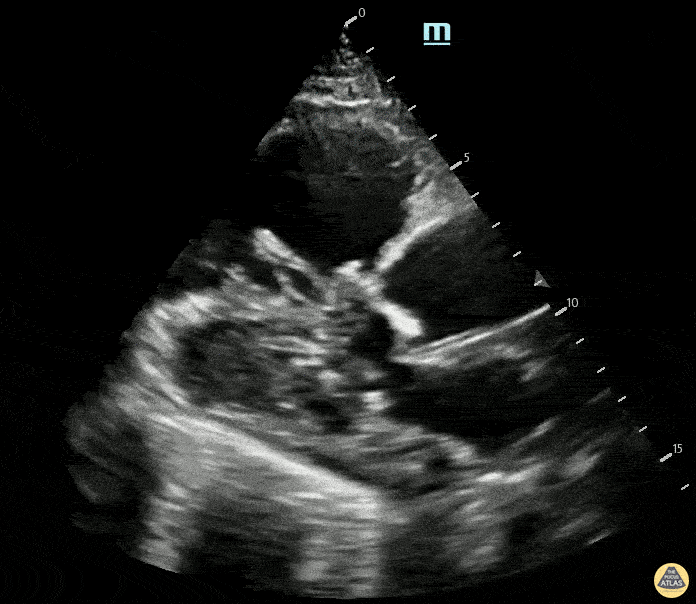

Right Ventricular Dysfunction - PSLA view demonstrating RV dilation and clot in transit

An elderly female presented with 3 days of shortness of breath. PSLA view identified severe RV dilation on bedside ultrasound prior to CT confirming saddle PE. Contributed by: Max Goder-Reiser, MD